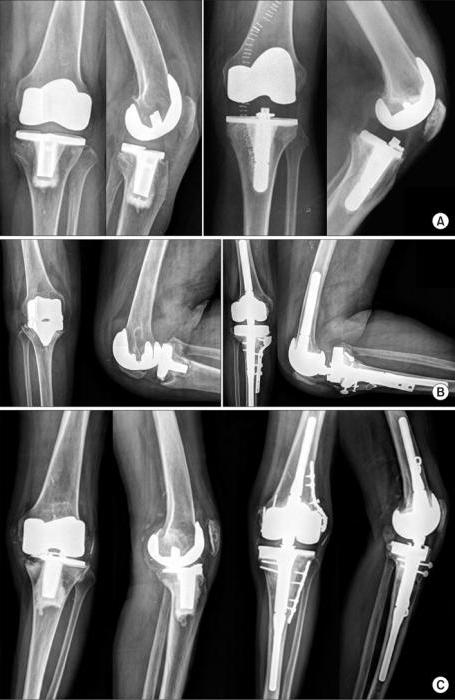

The second aspect is related to the dentures that will be delivered. It is usually assumed that those who go to the clinic at their own expense have a choice. People who receive an appointment for a quota can only rely on prostheses that are currently available in the institution. Of course, this is in any case better than nothing, especially for patients who objectively do not have the opportunity to pay for an operation that allows them to choose what and how to set. At the same time, no one can guarantee that at the right time, the doctors of the institution will have the best and most modern prostheses.

Prices, of course, are horrifying, but there is one aspect that scares many even more: the life of the prosthesis. Modern systems are not eternal help. Over the years, they gradually collapse. The term of operation is determined by several parameters. One of the most important is the method of attaching an artificial system to bone tissue. In some cases, the components of the prosthesis are literally hammered into the bone, and gradually the objects grow together. In medicine, this is called osseointegration. The joint elements when applying this technique are firmly fixed, so the system will last quite a long time.

The specified technique is far from always implemented. Often the quality of the bone simply does not allow such a prosthetics, but the reasons may be of a different kind. An alternative is the use of bone cement, that is, such a solidifying mass that allows you to quickly fix the prosthesis.

Friction pair

This parameter of the prosthesis directly determines the duration of its service life and the effect on the patient’s organic tissues. In fact, a joint is a joint whose components rub against each other. If in technology the process is smoothed by the presence of lubricant, then in the human body there is none, therefore, the components wear out over time. The degree of wear is directly related to the survival of the joint. It is determined by the materials used and the number of movements made by a person.

In order for the joint to live longer, it is necessary to install systems with the most effective friction parameters, as well as reduce the number of motion cycles. The longest wear periods are characteristic of systems in which ceramics are involved, but the price of such prostheses is also the highest.

What to choose?

Not every material is suitable for a particular patient. In some cases, polyethylene is the most profitable option; for others, ceramics will be the best solution. Sometimes doctors may advise resorting to metal prostheses. To choose the best option, you should seek the advice of an experienced doctor. Only a qualified specialist can evaluate all the positive, negative sides of different types of prosthesis in relation to a specific situation of a person, on the basis of which a reasonable decision will be made - both in quality and in financial investments.